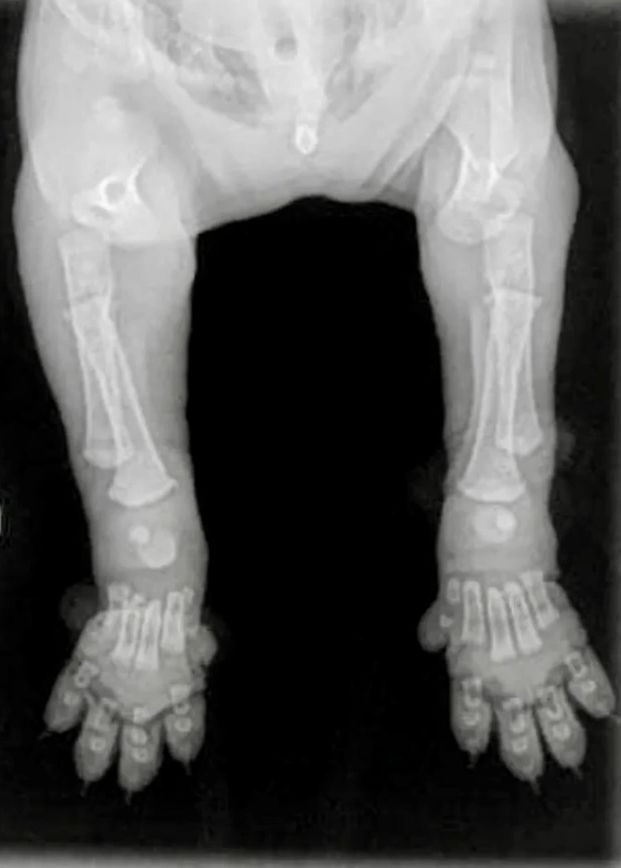

Complete Ossified Skeleton of a Dog Post Growth Plate Closure

From www.researchgate.net

Complete Ossified Skeleton of a Dog Post Growth Plate Closure Dog Growth Plate Closure in general, growth plates close when the dog fully matures (usually around 12 to 18 months of age). When can my puppy start agility? Does neutering impact a puppy's skeletal development? At what age do puppy growth plates close? growth of the epiphysis arises from two areas: What are growth plates in puppies? Once the dog has reached. Dog Growth Plate Closure.